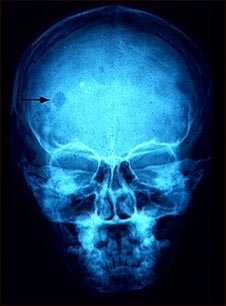

Granuloma eosinofílico- Radiografía del cráneo

Esta radiografía de cráneo muestra un granuloma eosinofílico, que es una lesión compuesta por un tipo de glóbulos blancos. La gravedad de esta condición puede variar desde una lesión única hasta la infiltración masiva de la piel, el hueso y los órganos corporales.